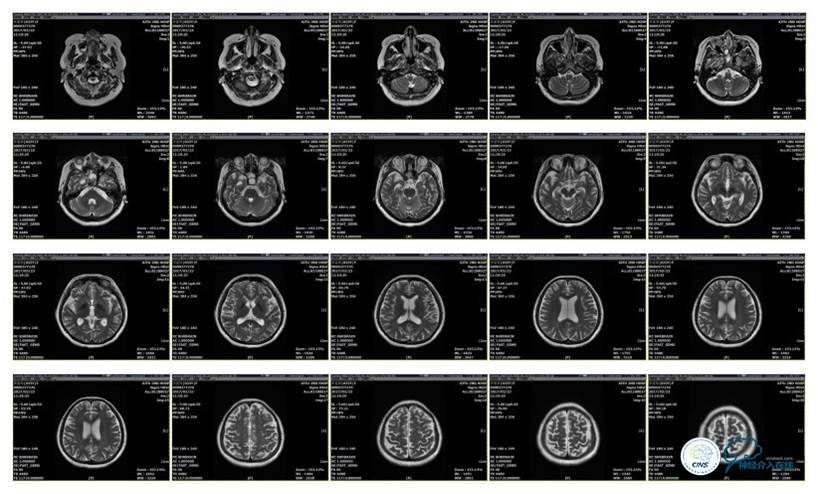

MRV

病史:患者于1年余前,因头部外伤在外院行头颅CT提示:未见异常。约3月后患者出现头痛、发作性意识丧失,在当地医院行头颅CT及MRI提示:未见明显异常。诊断为外伤性癫痫,予以对症治疗,未见明显好转。6月余前,无明显诱因出现鼻腔漏液,予以保守治疗,此后鼻腔间断漏液,漏液后头痛缓解。13天前因高热、恶心、呕吐在外院诊断为颅内感染(肺炎链球菌),予以抗炎等对症治疗2周后鼻漏停止,体温正常,CSF常规、生化正常,但头痛仍未缓解,转入我院神经内科治疗。反复腰穿颅内压450-500mmH2O左右,脑脊液常规及生化均正常。颅脑CT及MRI、MRV提示:左侧顶叶硬膜下血肿,鼻窦炎、乳突炎、左侧横窦、乙状窦闭塞、右侧横窦、乙状窦狭窄。予以华法林抗凝治疗2周,维持INR2-3,患者头痛仍无明显缓解,颅内压无降落,转入我科。

诊断:1、右侧横窦、乙状窦狭窄;2、硬膜下血肿(左侧顶);3、继发性癫痫;4、脑脊液鼻漏;5、颅内感染;6、乳突炎;7、鼻窦炎。

病理过程推理:首先是乳突炎—诱发左侧横窦乙状窦血栓最终闭塞,右侧横窦乙状窦狭窄—导致颅内高压,造成头痛及癫痫—持续颅内高压—皮层静脉回流受阻导致自发性硬膜下血肿及自发性脑脊液鼻漏—颅内感染。